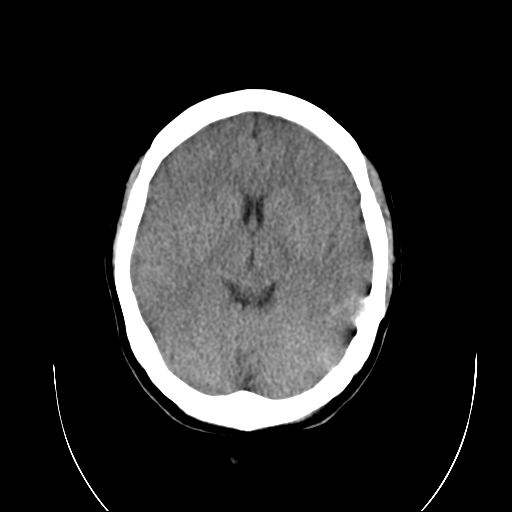

标题: CT18310:女,29岁,头部外伤后头疼、头晕十天。请会诊!! [打印本页]

标题: CT18310:女,29岁,头部外伤后头疼、头晕十天。请会诊!!

左顶叶裂隙样低密度灶,考虑什么呢??

外伤性脑肿胀。

脑沟裂池明显变窄,脑室变小。

个人认为诊断外伤性脑肿胀依据不足,首先是临床症状不太支持,第二是影像表现也不支持:年轻人脑室池可这样表现,弥漫性脑肿胀应有水肿导致的实质密度减低从而灰白质分界不清,而本例没有.至于左侧额叶后部裂隙样低密度影,考虑为脑沟,因与外侧脑沟相连.

个人认为诊断外伤性脑肿胀依据不足,首先是临床症状不太支持,第二是影像表现也不支持:年轻人脑室池可这样表现,弥漫性脑肿胀应有水肿导致的实质密度减低从而灰白质分界不清,而本例没有.至于左侧额叶后部裂隙样低密度影,考虑为脑沟,因与外侧脑沟相连.支持!建议短期复查!

调一下窗看看,右额顶部及左顶后部硬膜下象有出血!

左顶叶裂隙状低密度影为脑沟影,影像表现不考虑脑肿胀